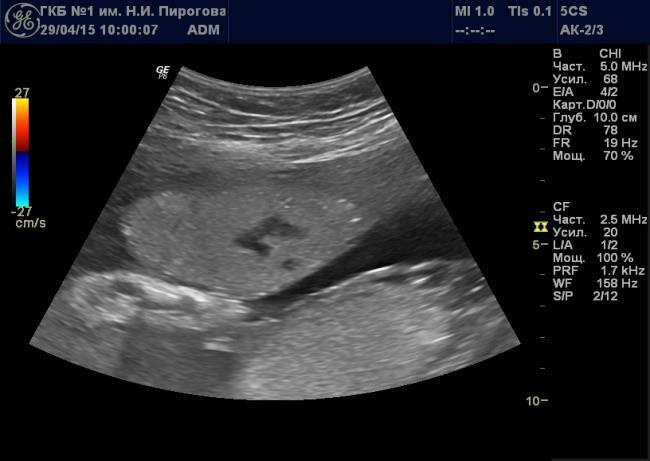

Выявляемые при серошкальном исследовании плаценты ан- или гипоэхогенные зоны чаще всего являются эхографическими срезами участков расширения ее МВП (Рис. 7) и значительно реже сосудов плода (Рис. 8). Расширение МВП может быть связано как с поступлением материнской артериальной крови, и отражать одно из состояний артериального капиллярного русла маточно-плацентарного кровотока (Рис. 9), так и с оттоком в материнское русло венозной крови (Рис. 10). При этом направление тока крови может быть установлено при цветовом допплеровском картировании (ЦДК). Следует иметь в виду, что венозное звено маточно-плацентарного кровообращения состоит из двух функциональных частей: венозных коллекторов плацентарного ложа возле разделительных септ и краевых синусов [10], которые также могут быть расширены (Рис. 11).

Рис. 9. Беременность 24 нед. Расширение межворсинкового пространства, связанное с артериальным притоком, в серошкальном режиме (а) и режиме цветового допплеровского картирования (б).

Рис. 10. Беременность 20 нед. Расширение межворсинкового пространства, связанное с венозным оттоком, в серошкальном режиме (а) и режиме цветового допплеровского картирования (б).